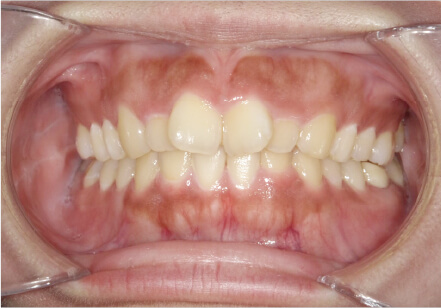

前歯前突の症例

8歳

男性

前歯が気になる

カウンセリング・診断結果

前突・叢生 アレルギー有

治療内容・方法

全額アライナー矯正 上下拡大装置使用

術後の経過・現在の様子

上下リンガルアーチ使用

費用・治療期間

780,000円、1年8ヶ月